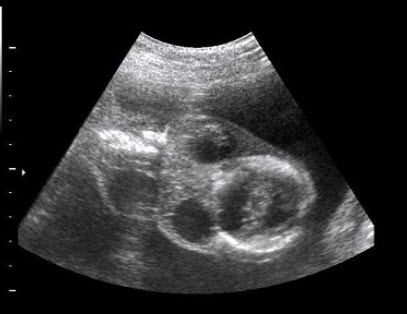

14、单项选择题

如图,最可能的诊断是()

A.软骨成长不全

B.致死性骨发育不全

C.窒息性胸廓发育不良

D.肢体屈曲综合征

E.无肢畸形